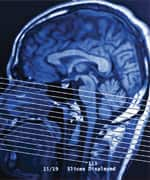

During the life span, the brain suffers from multiple sources of damage. As these effects accumulate, the result is often the development of neurodegenerative disorders, as well as the risk of stroke from progressive injury to brain blood vessels. Brain trauma is yet another way that the delicate microstructure of brain cells is disrupted, leading to loss of cognition and function.

While dementia, stroke, and brain injury may appear to be unrelated events, they all share fundamental processes that contribute to the eventual loss of brain cells and the decline in cognitive abilities.